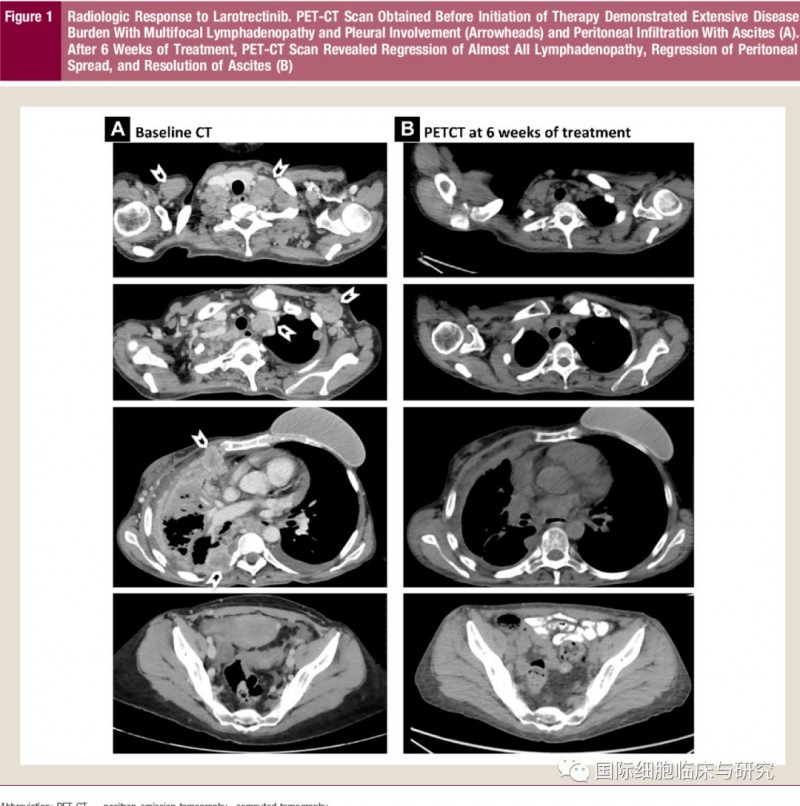

据《临床乳腺癌》杂志报道了一篇关于具有ETV6-NTRK3融合表达初次接受化疗的成人患者采用拉罗替尼治疗的临床研究,经6周治疗后患者PETCT显示肿瘤已消散大半。此外文章中还提及,乳腺分泌癌的肿瘤组织中超过90%的细胞都携带ETV6-NTRK3融合基因。所以,针对这种融合基因的靶向药物——拉罗替尼,对治疗分泌性乳腺癌有非常好的治疗效果。

图为患者治疗前CT及拉罗替尼治疗6周后PETCT对比图